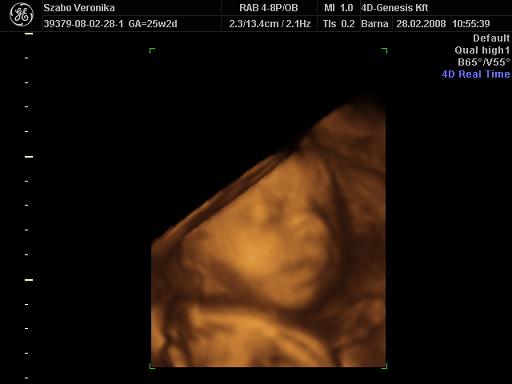

A doki szerint pufók kislány